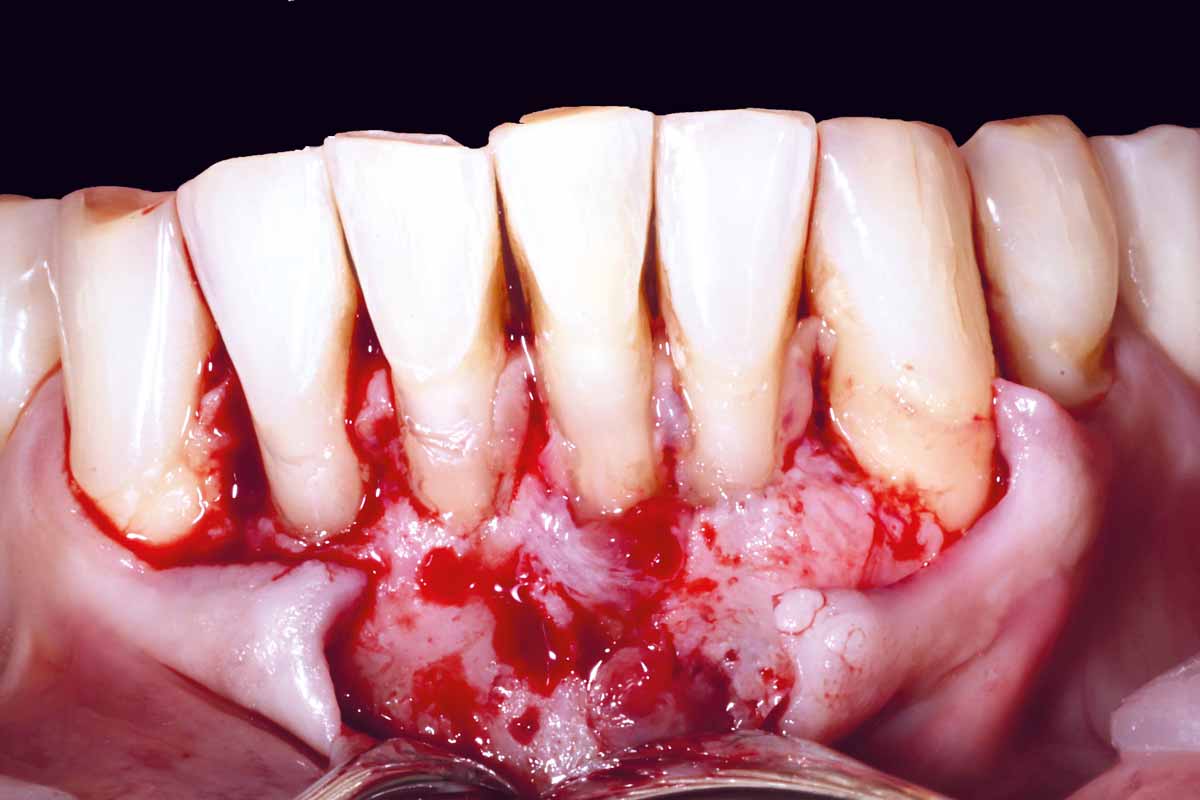

Pre-operative situation showing tooth 21 with deep periodontal pocket. Tooth presented with mobility grade III.